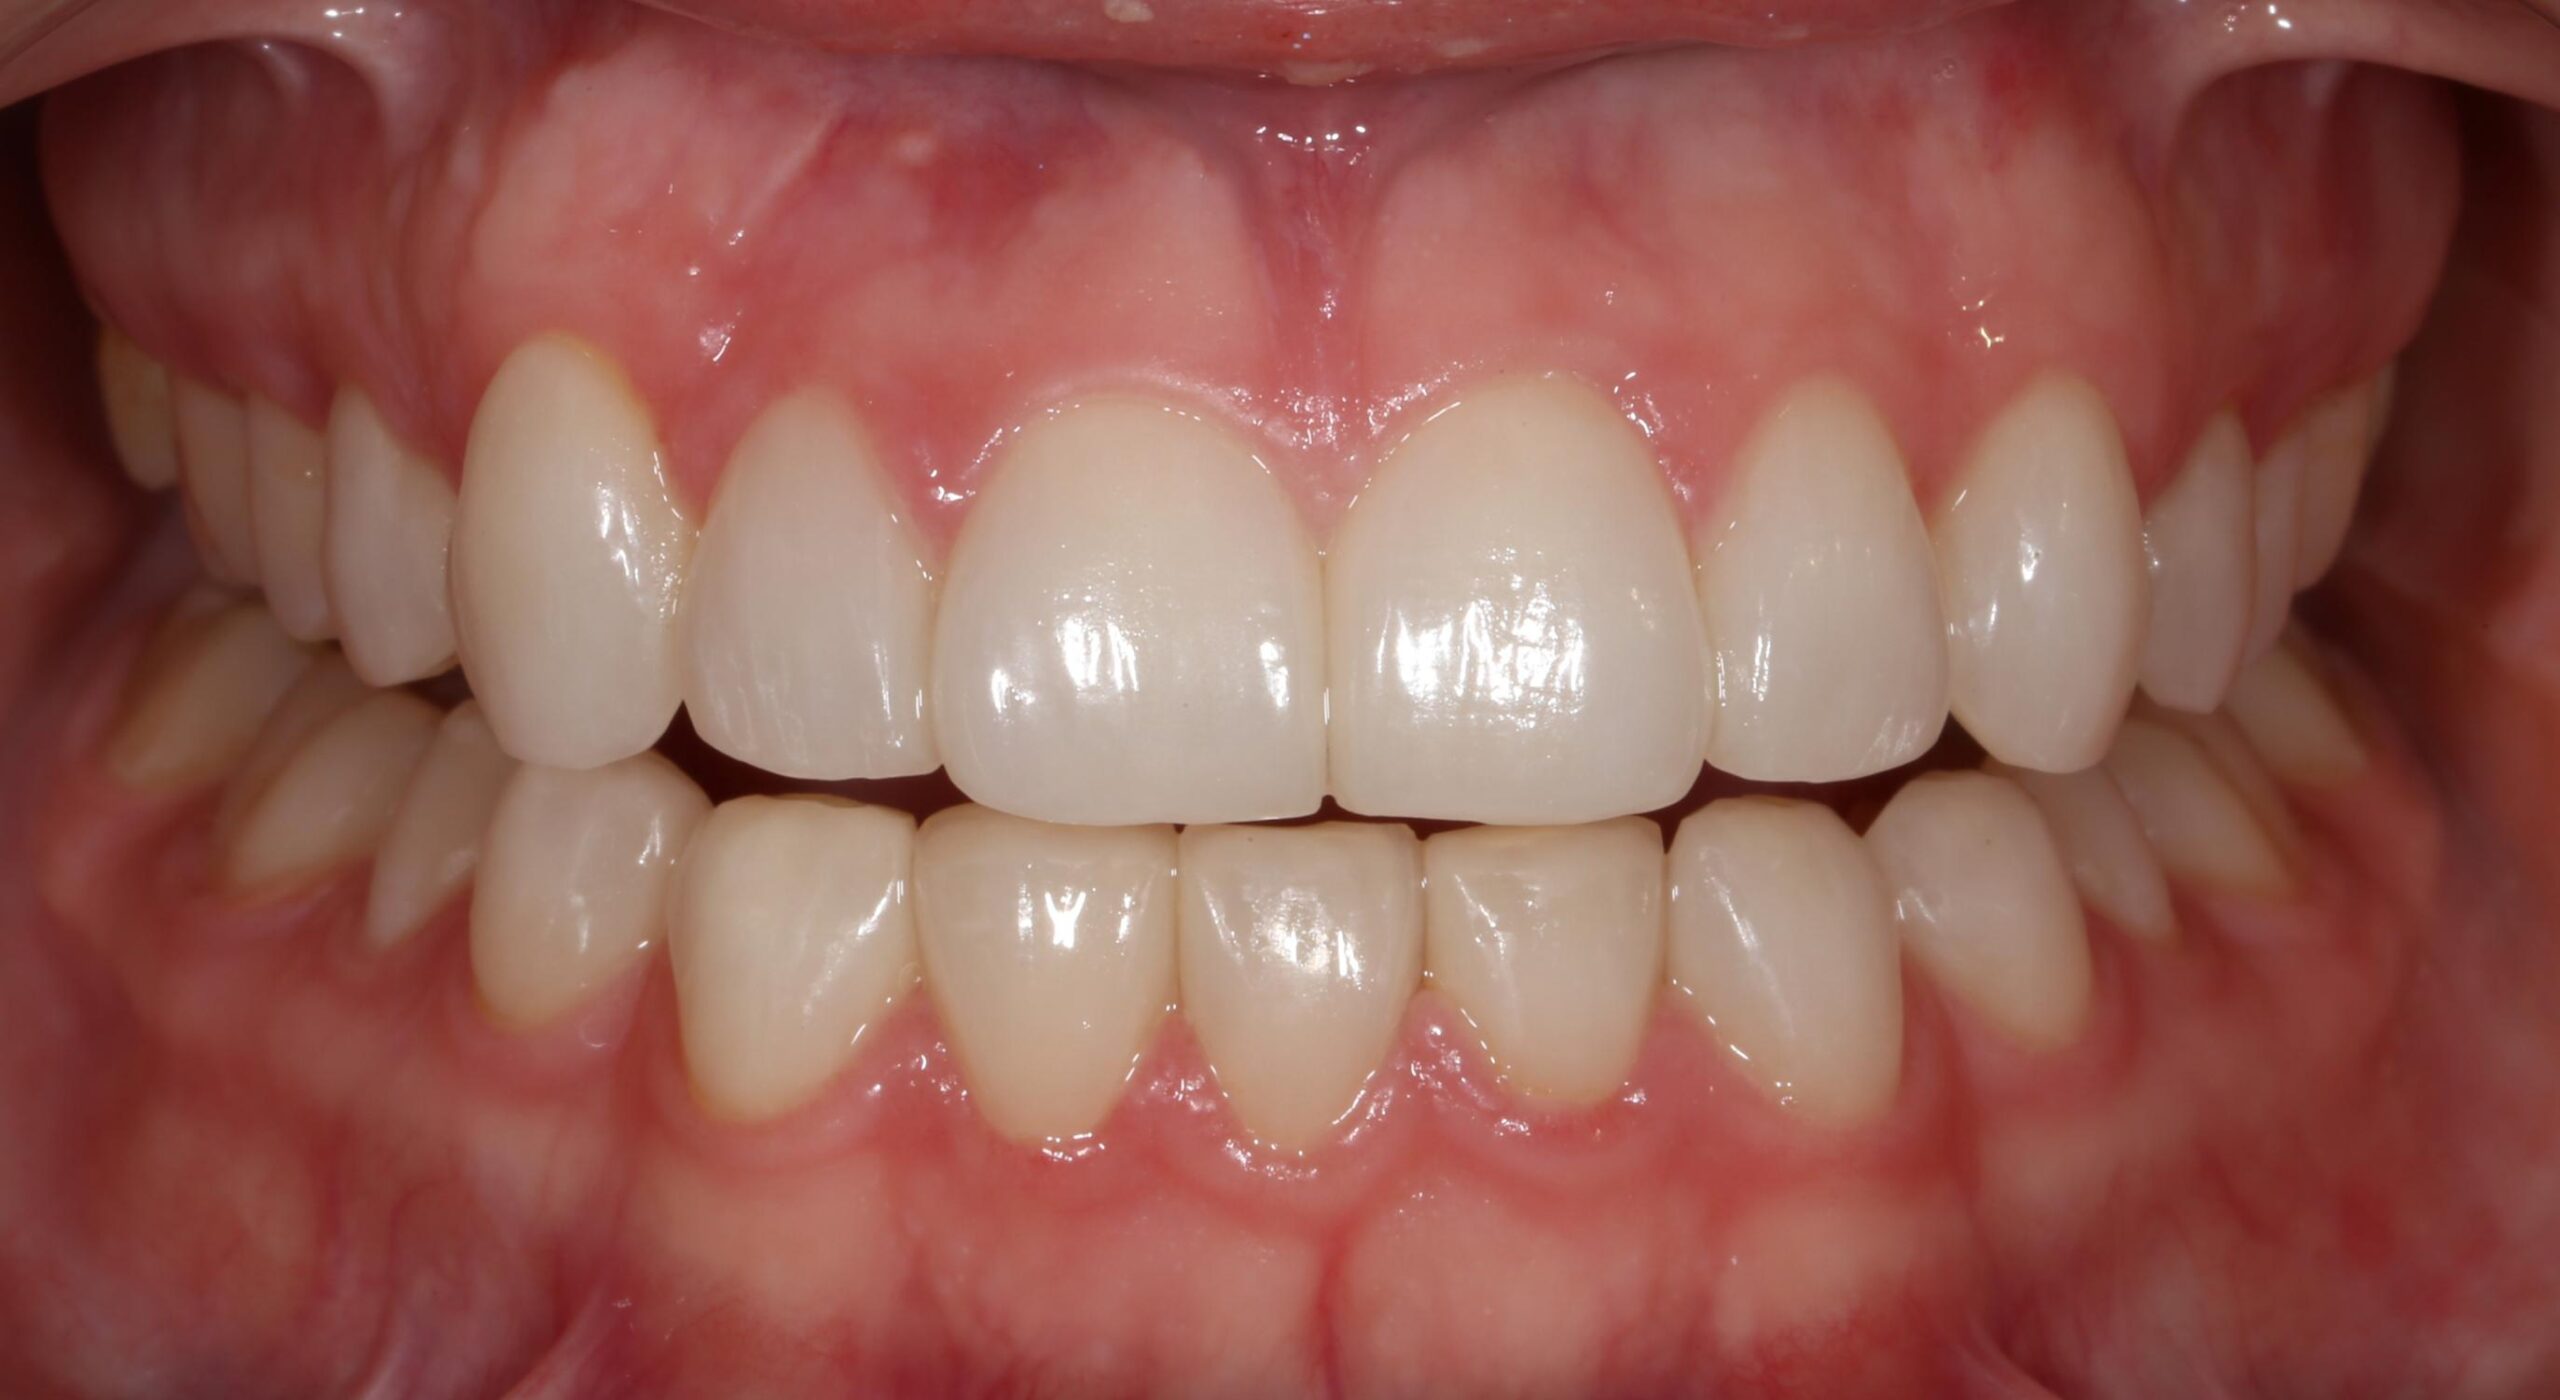

Esthetic Crown Lengthening

Before After

After Image